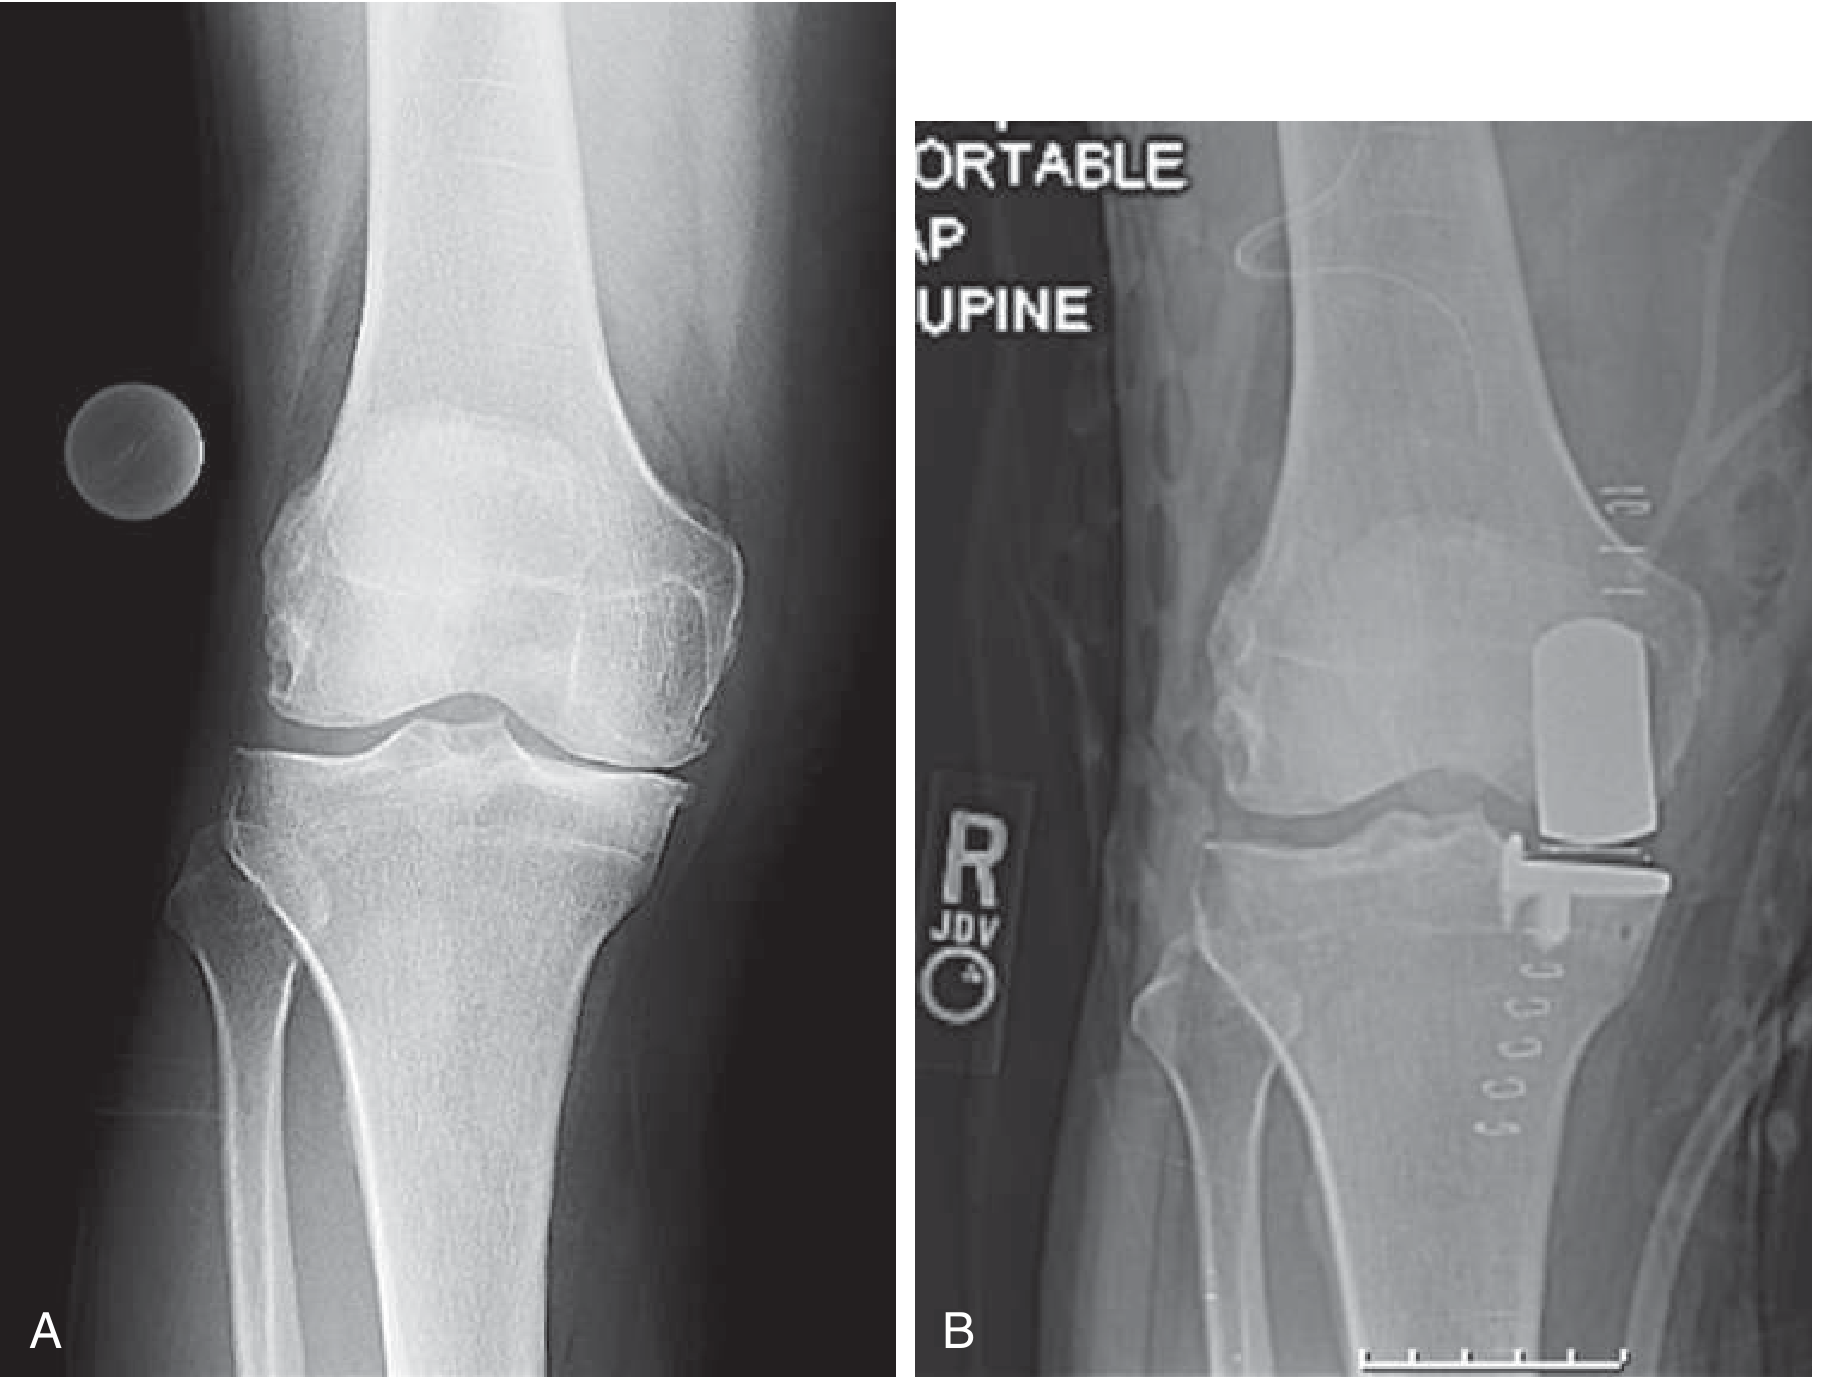

Medial unicompartmental knee replacement X-ray

Left: Knee with arthritis limited to the medial compartment. Right: After medial unicompartmental replacement. — Goldman-Cecil Medicine